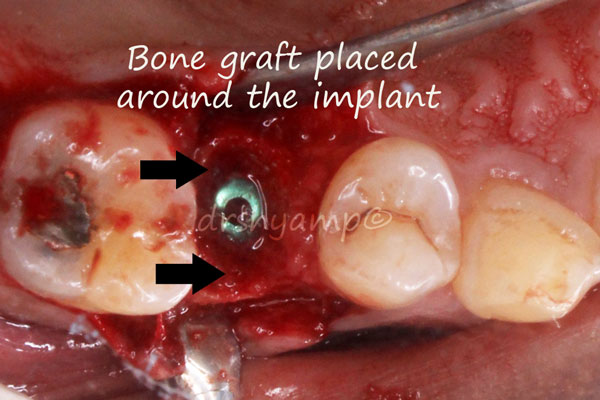

immediate dental implant

immediate dental implant

immediate dental implant

immediate dental implant

immediate dental implant

immediate dental implant

immediate dental implant

immediate dental implant

immediate dental implant